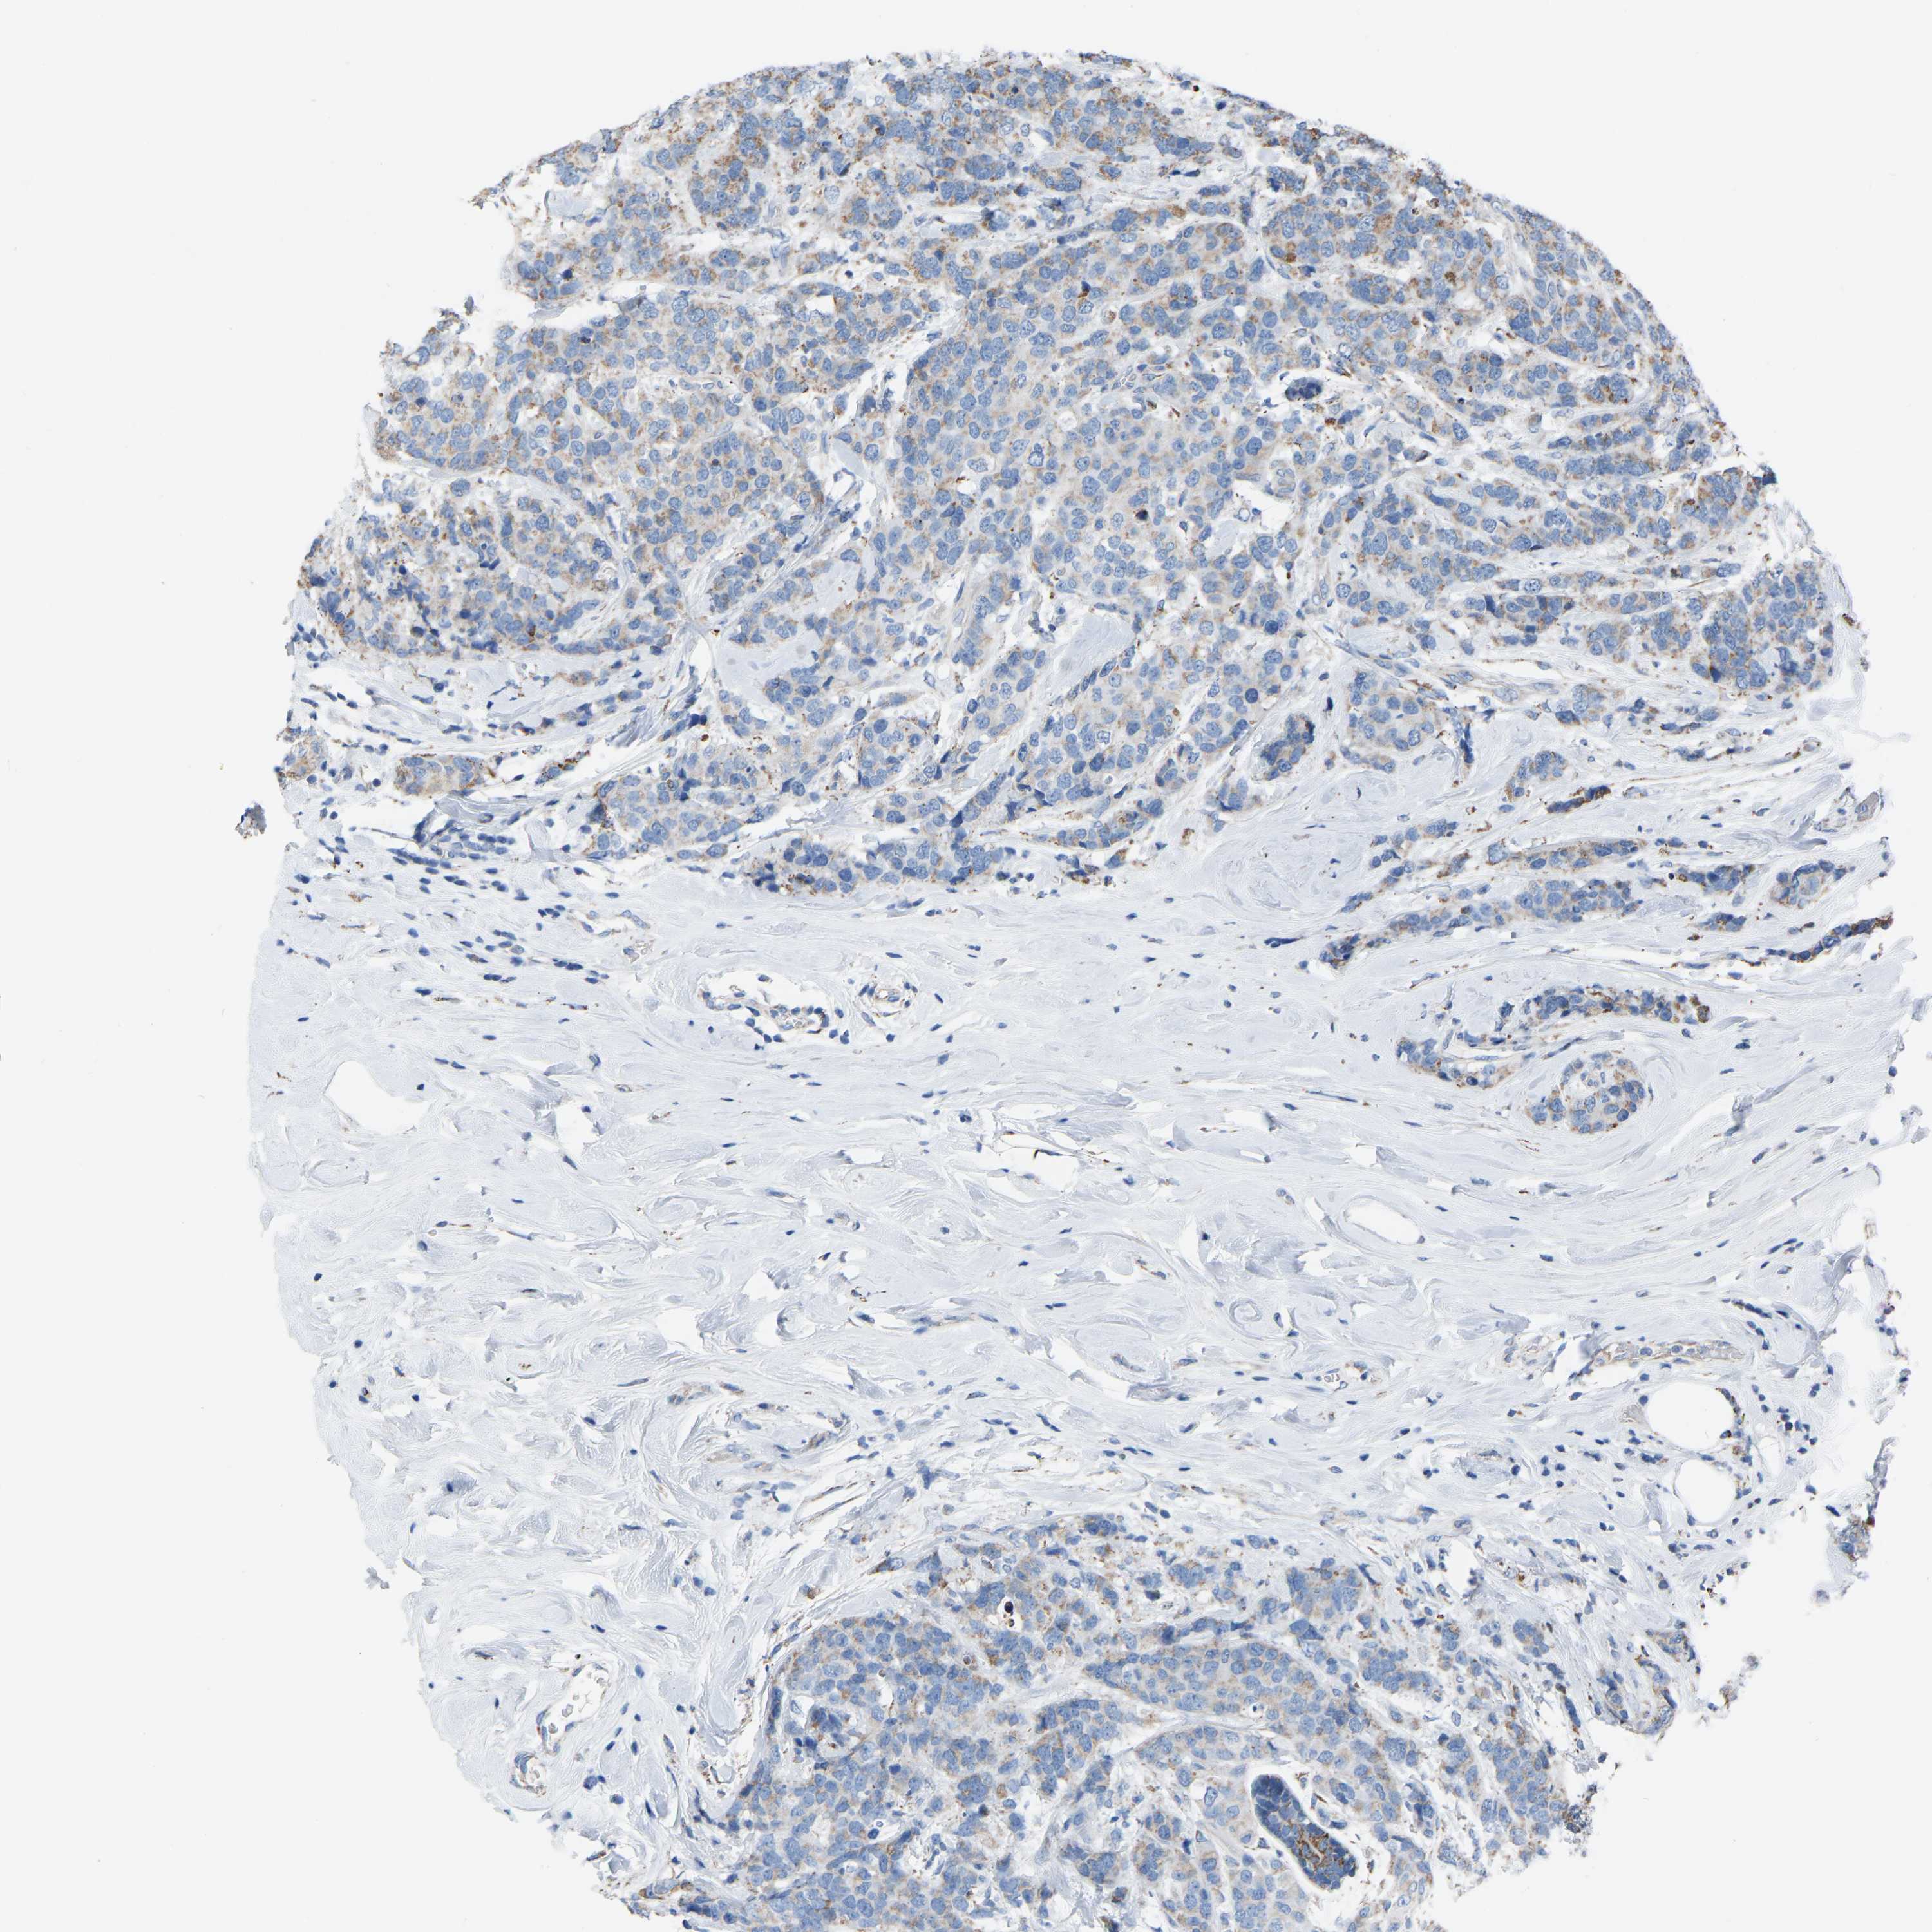

CANCER BREAST CANCER Show tissue menu

BRCA TCGA BRCA VALIDATION PROTEIN EXPRESSION